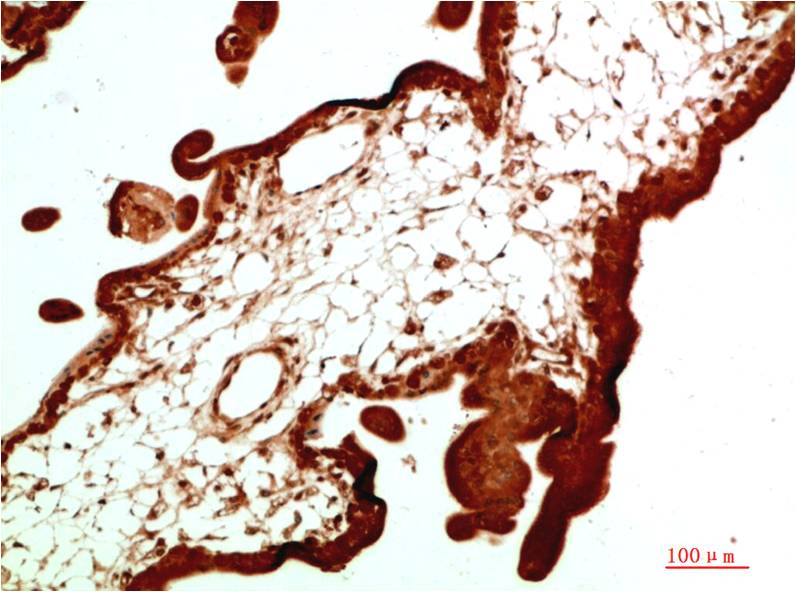

Applications :WB, IHC

| Recommended dilutions: | WB 1:500-2,000 IHC 1:50-300 |

| Specificity: | The antibody detects endogenous IkB α protein |